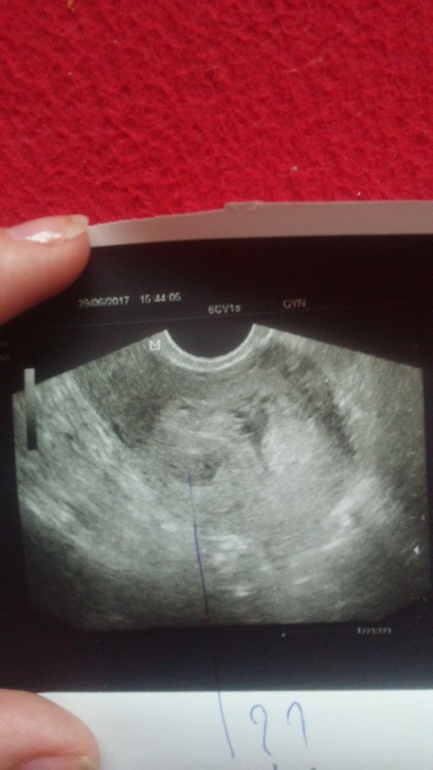

Двойня под вопросом.

Вопросы о беременных и для беременных двойнейВсем привет, сходила на узи срок 6 акушерских недель, на узи спросили двурогая ли у меня матка (нет), есть ли миома ( тоже нет), вообщем сказала что похоже на двойню. Так вот вопрос: Похож ли снимок на двоюню?

У меня почти такой же снимок двойни первый. Очень похоже. Да, смущает расстояние. Но очень похоже.

Оооочннь при очень похоже на двойню :)) единственное что смущает, это большое расстояние между ними..потому и спрашивает про двурогую матку...

Спасибо за ответ, ну двурогой точно никогда не была, еще больше запуталась, что же это раз далеко